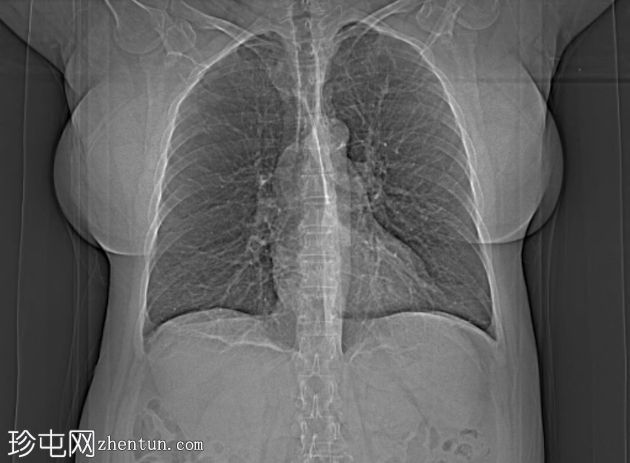

胸部

CT

双侧肺(尤其是上叶)广泛融合性小叶中心型肺气肿。

左上叶肺瘢痕形成,可能是先前感染的后遗症。

双侧乳房植入。

小叶中心型肺气肿是最常见的肺气肿形态学亚型。

早期小叶中心性肺气肿通常表现为小(<1 mm 至 3 cm)、圆形、均匀分布、边界不清的透亮区,可能出现在小叶中心动脉周围的次级肺小叶中央部分,而在严重的情况下,低衰减区会融合且不可分离,并且失去小叶中心分布。